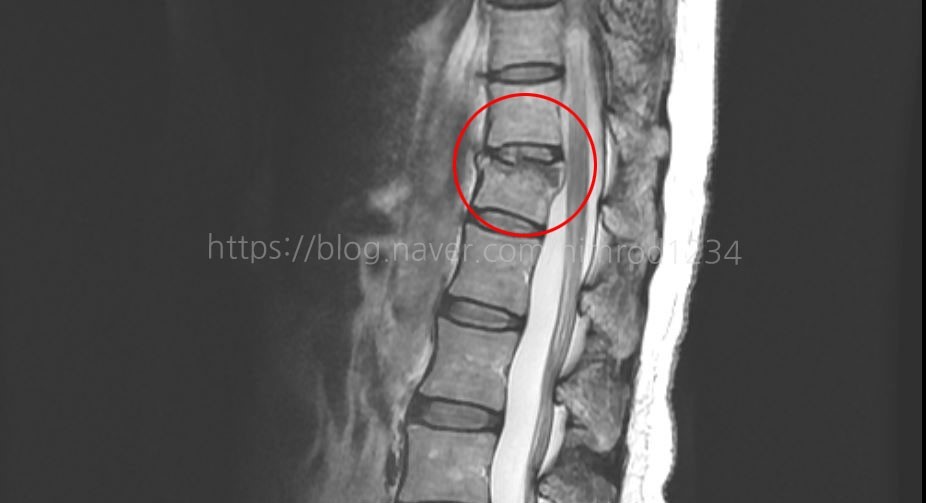

압박골절 ; 골다공증이 있는 노인은 아주 위험한 골절

압박골절은 뼈가 눌려서 부저리는 골절입니다. 압박골절은 뼈가 눌리는 힘이 강할 때 발생하며, 주로 척추뼈의 앞기둥에서 발생합니다. 압박골절은 뼈가 납작하게 눌려서 부러지는 것이 특징입니다. 1. 압박골절 원인 1) 낙상 : 낙상 시 축추에 큰 충격이 가해져 압박골절이 발생할 수 있습니다. 2) 사고 : 교통사고, 산업재해 등 사로로 인해 척추에 큰 충격이 가해지면 압박골절이 위험성이 증가합니다. 3) 질병 : 골다공증, 퇴행성 척추 질환, 종양 등이 있는 경우 압박골절이 발생할 위험이 높아집니다. 2. 증상 1) 통증 : 가장 흔한 증상으로, 통증은 척추 부위에서 발생하고, 심한 경우 앉거나 서 있기가 어려울 정도로 심할 수 있습니다. 2) 감각 이상 : 압박골절로 척추 신경이 손상되면, 배뇨 곤란 등 ..